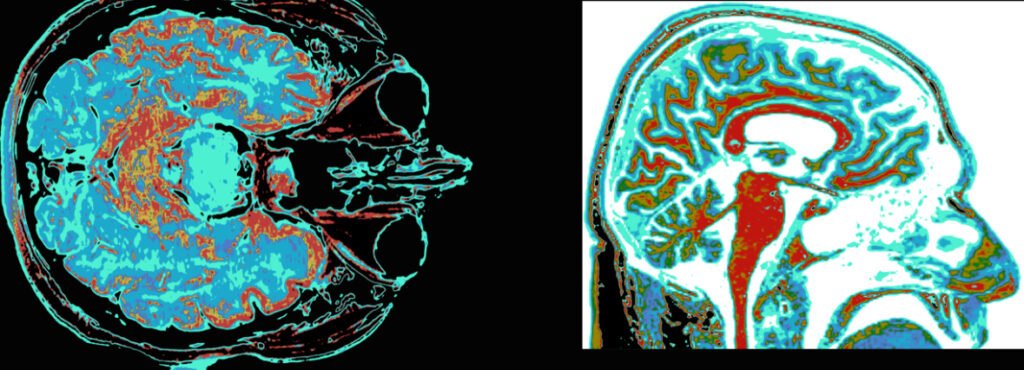

🧠 The Human Brain Without Fear

Fear is deeply connected to memory, learning, and decision-making. Removing it would change how the brain functions.